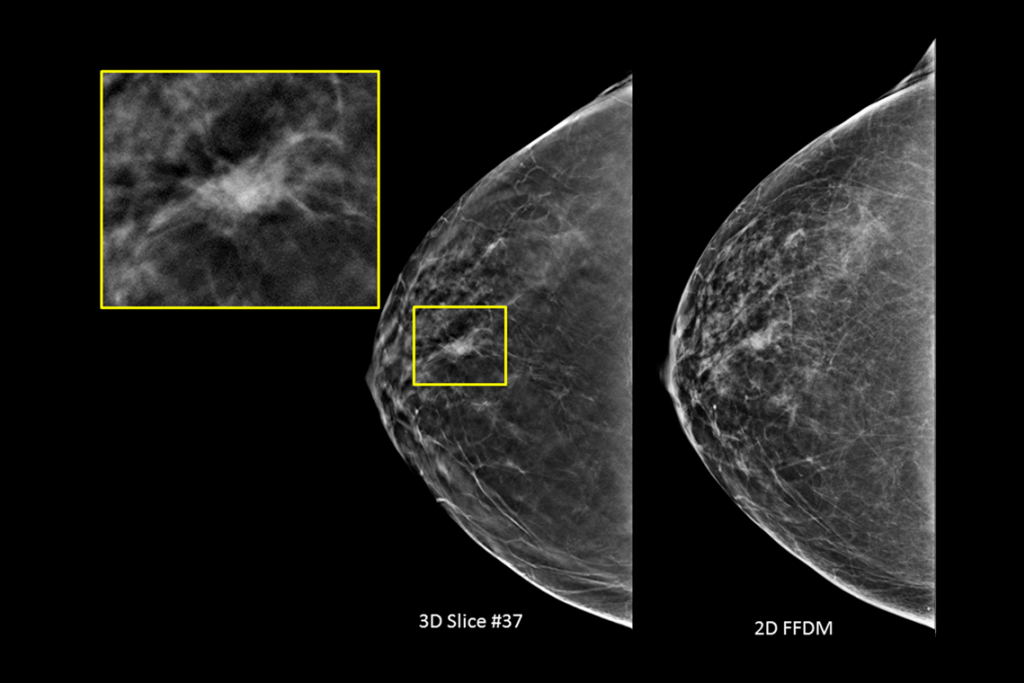

Klinische beelden van borstscan met verdachte laesie